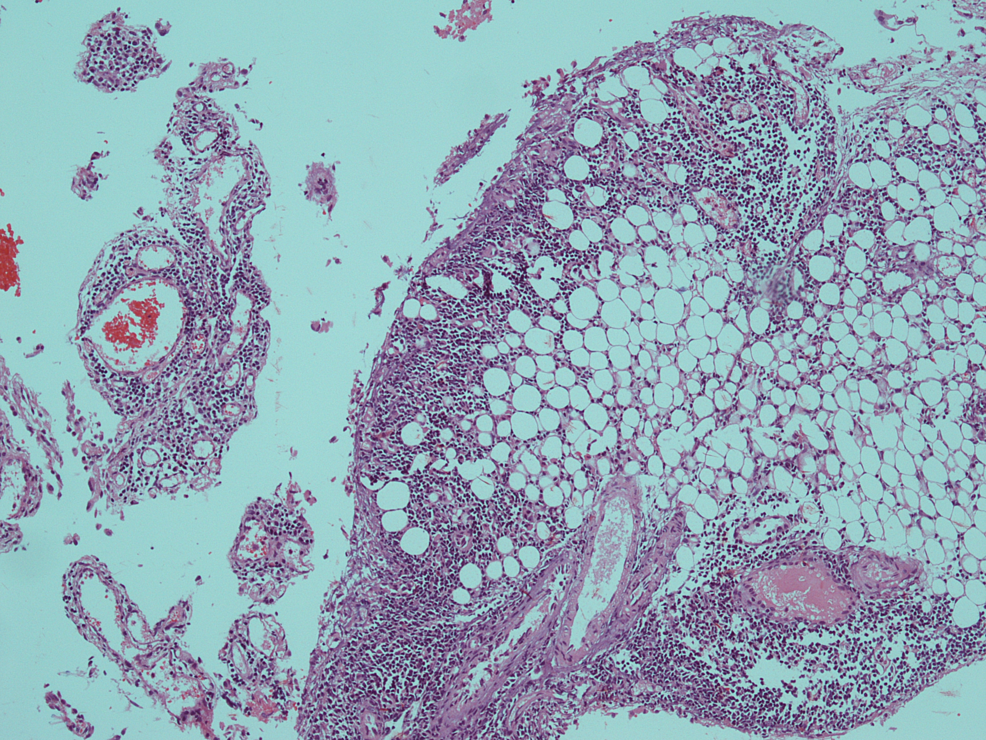

Ultimately CT abdomen showed gross ascites with omental thickening and nodularity (Figures 1-2). A laproscopic omental biopsy was performed. Grossly omentum and gut loops appeared normal. However, omental biopsy showed atypical lymphoid infiltrate (Figure 3). Immunohistochemistry showed lymphocytes positive for CD20 and Tdt while CD10 negative (Figures 4-5). In correspondence with these results precursor B-cell lymphoblastic lymphoma was diagnosed. After discussing the biopsy report with the child’s parents CHOP therapy has been initiated.